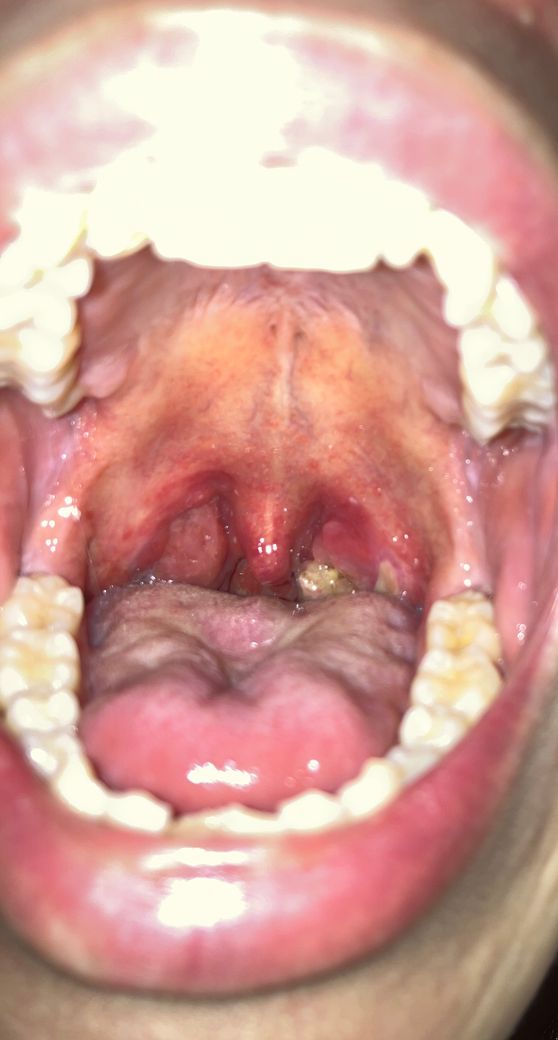

인후두염인거 같은데 병원에 가면 무슨 조치가 될까요

어느날 하루 무리를 해서 그런가 구내염에 쎄게 왔는데 상태는 이렇구요 현재 침삼킬때마다 약간 통증이 있습니다

현재 약국에서 치료형 가글 알약 알보칠 한번씩 바기 를 하면서 집에서 최대한 조치하고 있는데 병원에 가면 이런 약 처방 말고 해주실수있는게 있을까요..

• 1번 째 사진

말씀하신 것처럼 알보칠을 통한 치료 효과를 기대해 볼 수 있겠지만, 자세한 원인 확인을 위해서 사진 상의 병변 부위에 대한 배양검사를 진행하여 특정 세균이 검출되면 항생제 치료를 통해 치료 기간을 단축시킬 수 있습니다. 항생제의 경우 병원에서 처방이 필요한 약제로 진찰 후에 처방받을 수 있습니다.